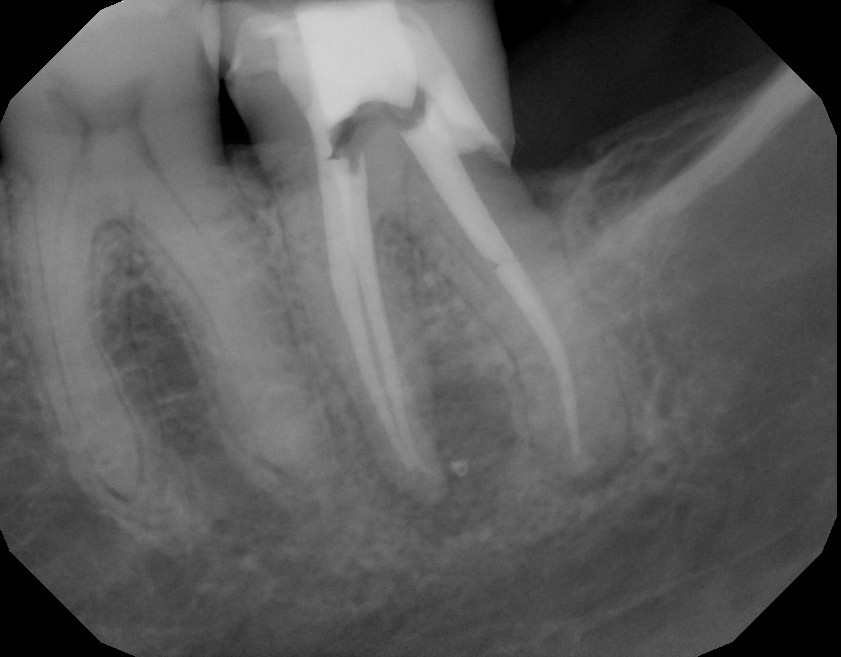

The following example is a root canal that was done 13 months ago by an associate dentist in a general dental practice.  This can sometimes create a difficult situation for the owner dentist, when the patient returns with an abscess a year later. Unfortunately for the patient, this root canal was destined to fail.  With missed canals and short obturation, this treatment was incomplete.

Root canal done 13 months earlier.  Large periapical lesion on mesial root.  Short root canal filling on mesial canals.  The prognosis for this tooth was poor at the time of completion because the MB canal was not cleaned and obturated. Bacterial left behind will continue to cause periapical disease.

CBCT shows missed MB canal and short ML canal filling.